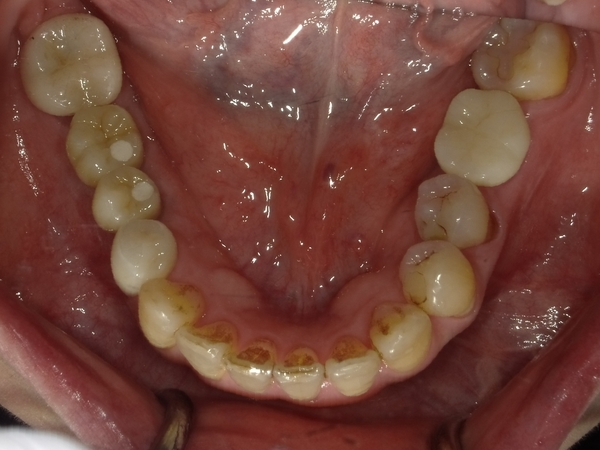

ガタガタとした歯並びや八重歯(叢生)CASE75